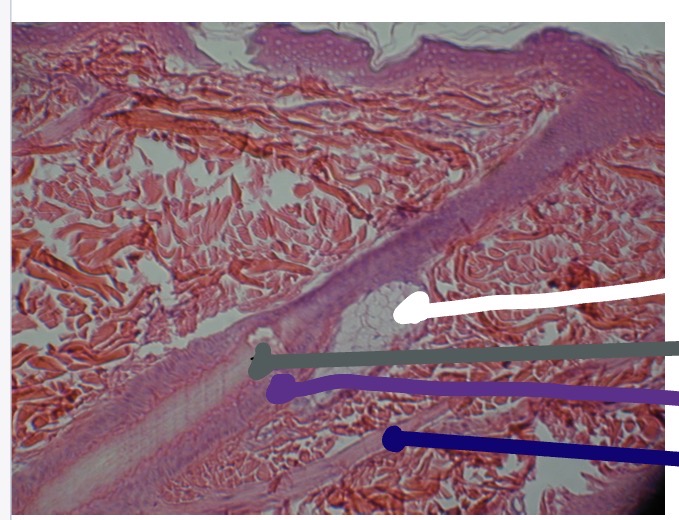

<p>What’s the yellow line in this photo</p>

What’s the yellow line in this photo

Hair Shaft

<p>What the orange line in this photo</p>

What the orange line in this photo

Hair root

<p>What’s the dark blue line in this photo</p>

What’s the dark blue line in this photo

Hair follicle

<p>What’s the blue line in this photo</p>

What’s the blue line in this photo

Sebaceous gland

<p>What is the white line in this photo</p>

What is the white line in this photo

<p>What is the grey line in this photo</p>

What is the grey line in this photo

<p>What is the purple line in the photo</p>

What is the purple line in the photo

<p>What is the dark blue line in this photo</p>

What is the dark blue line in this photo

Arrector Pili muscle